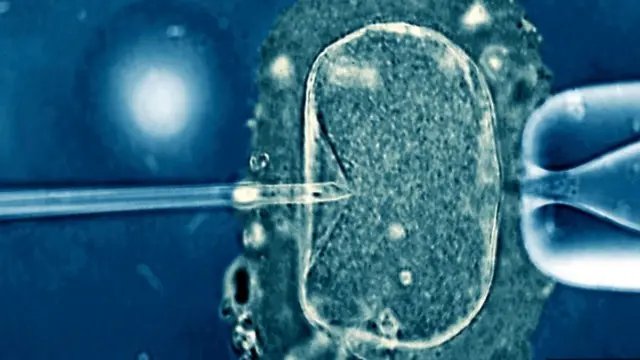

لكن هذه التقنيات لا تزال تعتمد على عمر البويضة، لا بسبب تأثير الشيخوخة على الحمض النووي فحسب، بل أيضا لأن البويضات تتعرض مع مرور الوقت لملوثات بيئية متزايدة. ومن الممكن في المقابل إجراء الإخصاب في المختبر باستخدام بويضة من متبرعة شابة. وتتيح الآن معظم عيادات علاج العقم حول العالم للنساء إمكانية تخزين بويضاتهن أو تجميدها حتى يصبحن مستعدات للحمل، عندها تلقح البويضة وتزرع في أرحامهن.

ويقول ويلز إن صعوبة الحمل في سن متقدمة لا تكمن في تدهور الرحم، إنما في تدني نوعية البويضة، وتحديدا الشذوذ الصبغي، فالبويضة هي البذرة التي يعتمد عليها الجنين في تنفيذ الكثير من العمليات المطلوبة في مراحل تطوره الأولى.

ويعكف ويلز وزملاؤه من الأخصائيين في علم الأجنة على تطوير تقنيات لاختيار أفضل البويضات لاستخدامها في علاجات الإخصاب في المختبر، مثل الفحص الوراثي قبل زراعة البويضة. وتساعد عمليات استبدال الميتوكوندريا في علاج العيوب في البويضات لمساعدة الأمهات على إنجاب أطفال أصحاء.